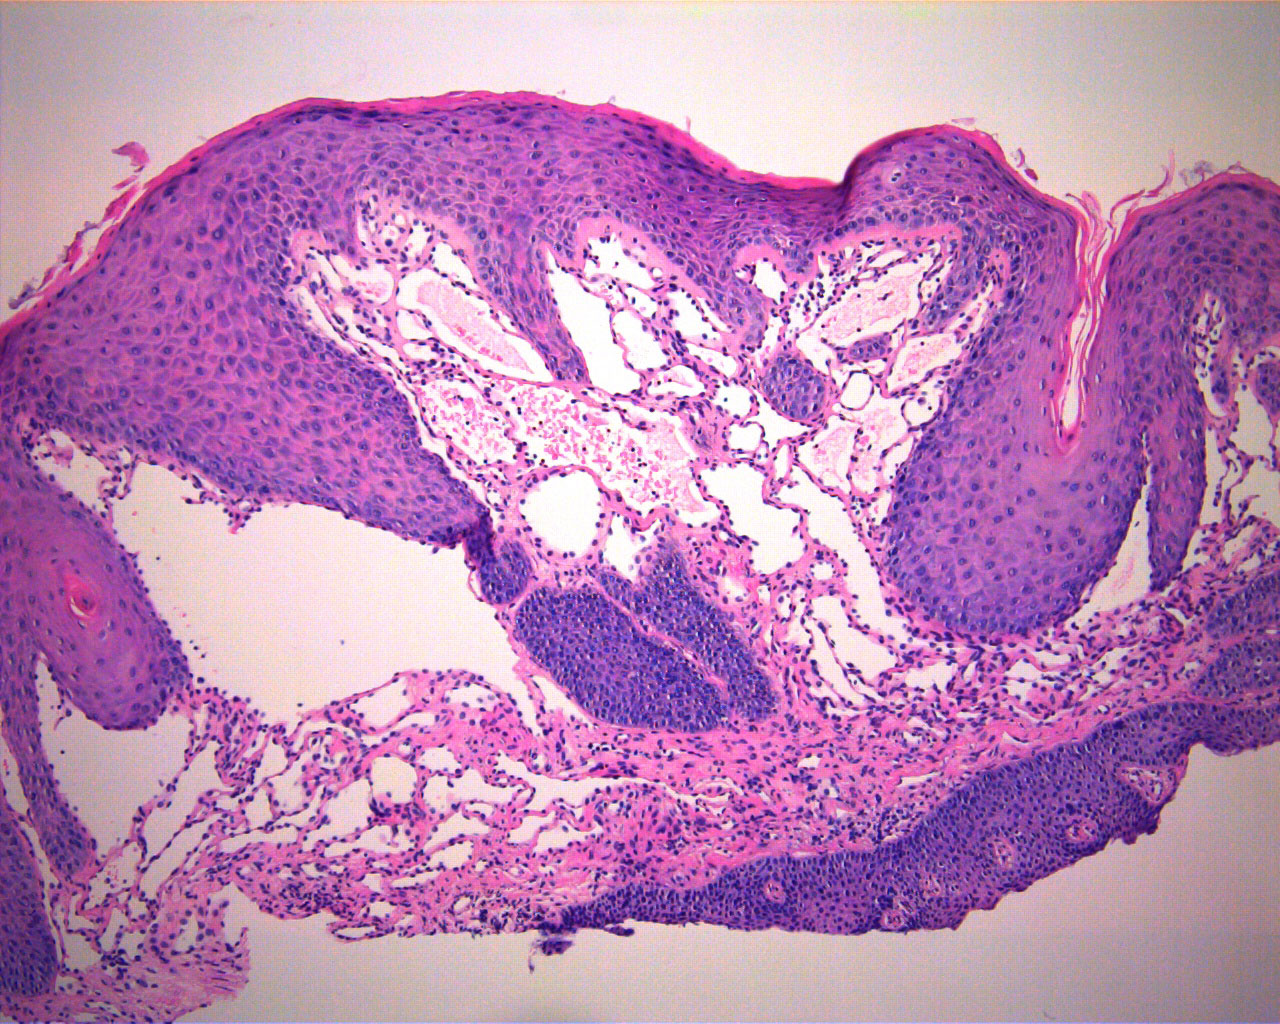

Localized juvenile spongiotic gingival hyperplasia Microscopic Spongiotic Gingival Hyperplasia Localized juvenile spongiotic gingival hyperplasia (ljsgh) is a gingival lesion with unique clinicopathologic features that may. Localized juvenile spongiotic gingival hyperplasia (ljsgh) is a recently described uncommon and distinctive. Localized juvenile spongiotic gingival hyperplasia (ljsgh) is an uncommon entity with unknown etiology. Within the last 10 years, humans, english, clinical. Localized juvenile spongiotic gingival hyperplasia, and pyogenic granuloma; A new. Spongiotic Gingival Hyperplasia.

Localized juvenile spongiotic gingival hyperplasia Microscopic Spongiotic Gingival Hyperplasia Within the last 10 years, humans, english, clinical. A new pathological entity with distinct clinicopathological features has been recently described and termed as juvenile. Localized juvenile spongiotic gingival hyperplasia (ljsgh) is an inflammatory lesion that presents as an area of edema and erythema involving marginal and/or attached. Localized juvenile spongiotic gingival hyperplasia (ljsgh) is a gingival lesion with unique clinicopathologic. Spongiotic Gingival Hyperplasia.

Localized juvenile spongiotic gingival hyperplasia Microscopic Spongiotic Gingival Hyperplasia Localized juvenile spongiotic gingival hyperplasia (ljsgh) is a gingival lesion with unique clinicopathologic features that may. A new pathological entity with distinct clinicopathological features has been recently described and termed as juvenile. Within the last 10 years, humans, english, clinical. Localized juvenile spongiotic gingival hyperplasia (ljsgh) is a recently described uncommon and distinctive. Localized juvenile spongiotic gingival hyperplasia (ljsgh) is. Spongiotic Gingival Hyperplasia.

Localized juvenile spongiotic gingival hyperplasia Microscopic Spongiotic Gingival Hyperplasia Localized juvenile spongiotic gingival hyperplasia (ljsgh) is a gingival lesion with unique clinicopathologic features that may. Localized juvenile spongiotic gingival hyperplasia (ljsgh) is a recently described uncommon and distinctive. Localized juvenile spongiotic gingival hyperplasia (ljsgh) is an uncommon entity with unknown etiology. Localized juvenile spongiotic gingival hyperplasia, and pyogenic granuloma; A new pathological entity with distinct clinicopathological features has been. Spongiotic Gingival Hyperplasia.

Localized juvenile spongiotic gingival hyperplasia Microscopic Spongiotic Gingival Hyperplasia Localized juvenile spongiotic gingival hyperplasia (ljsgh) is an inflammatory lesion that presents as an area of edema and erythema involving marginal and/or attached. Localized juvenile spongiotic gingival hyperplasia (ljsgh) is a gingival lesion with unique clinicopathologic features that may. Within the last 10 years, humans, english, clinical. Localized juvenile spongiotic gingival hyperplasia (ljsgh) is an uncommon entity with unknown etiology.. Spongiotic Gingival Hyperplasia.